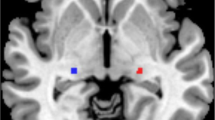

The thalamic subregions were defined according to a connectivity-based parcellation study using multimodal neuroimaging techniques [29]. In each hemisphere, the thalamus was parcellated into the medial prefrontal thalamus (mPFtha), premotor thalamus (mPMtha), sensory thalamus (Stha), rostral temporal thalamus (rTtha), posterior parietal thalamus (PPtha), occipital thalamus (Otha), caudal temporal thalamus (cTtha), and lateral prefrontal thalamus (lPFtha). Thus, we defined a total of 16 regions of interest (ROIs) for the bilateral parts of the thalamus (Fig. 1).

Illustration of subregions of the bilateral thalami. Abbreviations: mPFtha, medial prefrontal thalamus; mPMtha, premotor thalamus; Stha, sensory thalamus; rTtha, rostral temporal thalamus; PPtha, posterior parietal thalamus; Otha, occipital thalamus; cTtha, caudal temporal thalamus; lPFtha, lateral prefrontal thalamus; L, left; R, right